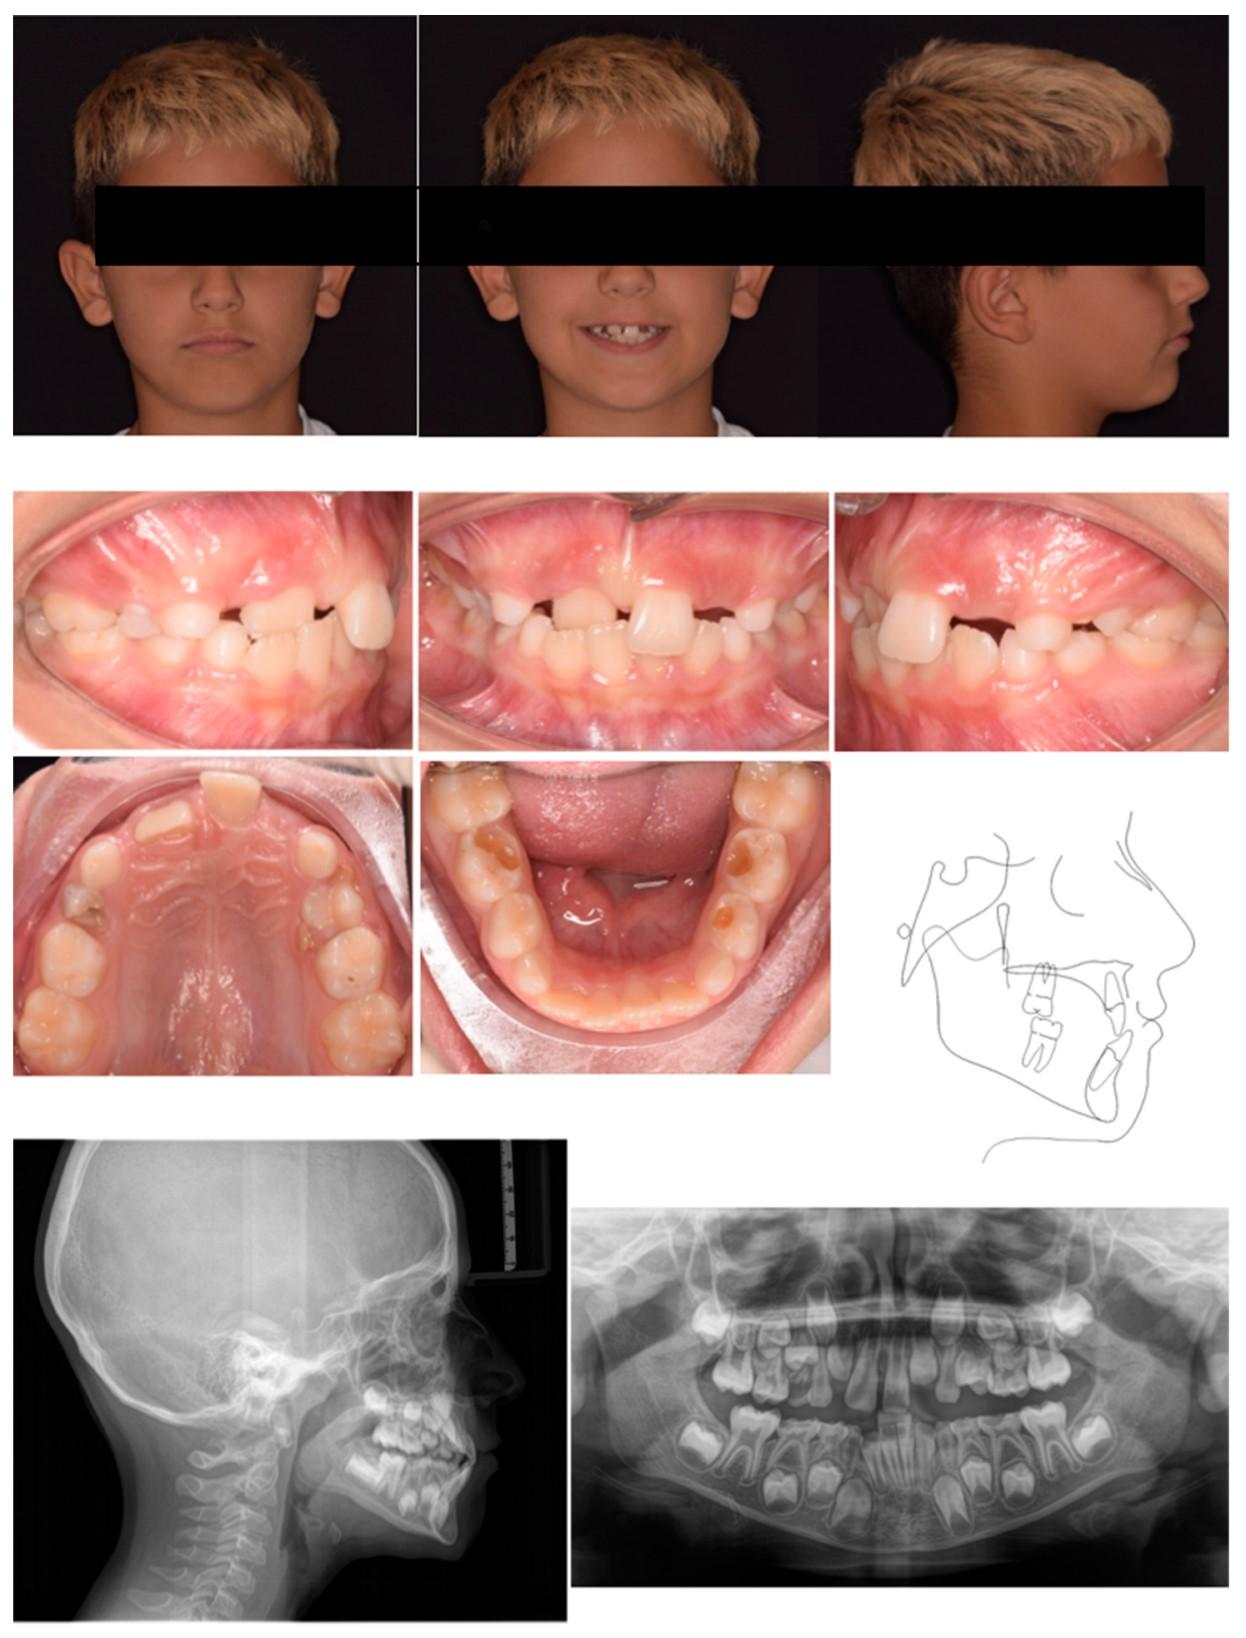

Shark teeth je kolokvijalni naziv za pojavu kod djece kada stalni zubi izbijaju iza mliječnih zuba, a da mliječni zubi nisu prethodno ispali, čime se stvara dvostruki red zuba, slično zubima ajkule (slika 1,2).

Najčešće se javlja na donjim prednjim zubima (sjekutićima), ali se može desiti i na gornjim zubima. Najčešće se primjećuje kada dijete navrši 6 godina- tokom rane mješovite denticije, ali se može javiti i kasnije. Nepravilno nicanje donjih stalnih sjekutića je posljedica velikih zuba i uskih vilica i znak su poremaćaja u postavi zuba koji se naziva tjeskoba. U poslednje vrijeme često se javlja kod djece, i izaziva zabrinost kod roditelja.

Slika 1. Stalni lijevi centralni sjekutić iza mliječnih sjekutića

Slika 2. Stalni lijevi i desni centalni sjekutić iza mliječnih sjekutića